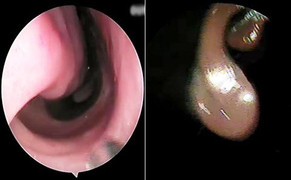

Phần amidal bị viêm nặng, sưng tấy đỏ sần sùi, nổi cục như chùm nho chèn kín đường thở người đàn ông 35 tuổi, anh này phải đi cấp cứu vì ngạt không thở được.